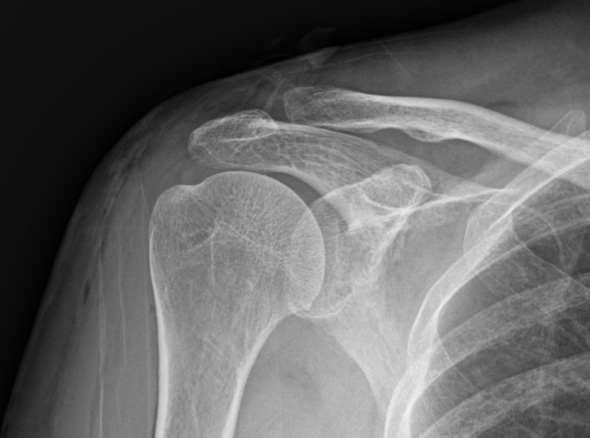

비수술 치료

주사 흡인술

체외충격파치료

도수치료

수차례 충격파 치료 등에도 호전되지 않는 경우

주사 흡인술이 가능하지 않은 경우(오래되거나 딱딱한 석회)

1-2Cm 이상의 큰 석회

운동 범위의 감소가 매우 큰 경우

힘줄 파열이 동반되어 있는 경우